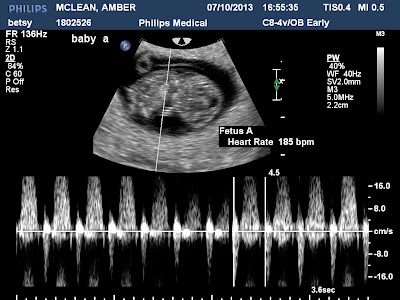

Baby A measured at 9 weeks, 4 days. Right on target. This baby has actually gained a few days, because it was a few days behind last time. Heart rate was 185. Perfect!

Now for the u/s pics: